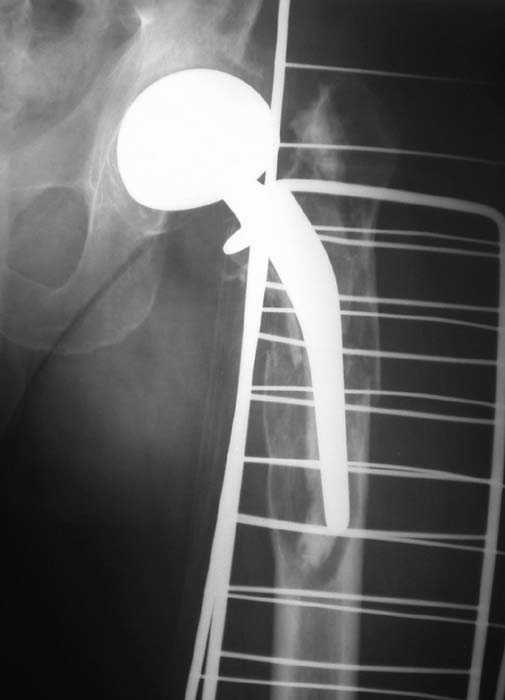

Мужчина, 39 лет.По поводу двустороннего асептического некроза головок бедренных костей последовательно выполнено тотальное эндопроезирование левого (1998 г), затем правого (1999 г) тазобедренных суставов.

26/06/06

С 2001 г отмечает нарастающие боли в левом бедре. Предполагается удаление протеза, удаление цемена из канала бедра, пластика дефекта бедренной кости.

Нет никакого смысла делать операцию в два этапа. С чашкой все понятно - стандартный подход с установкой пресс-фит компонента. На бедре имеет

место перипротезный перелом В3 типа - т.е. перелом вокруг ножки с ее нестабильностью на фоне выраженного остеолиза. Решение - доступ к каналу

через перелом с удалением самой ножки, костного цемента и рубцовых тканей. Установка ножки дистальной фиксации (типа Solution), длину ножки

надо определить по шаблону. Минимальный контакт ножки с интактной костью - 6-8 см. Фрагменты проксмального отдела собираются на ножке

эндопротеза, дефекты костной ткани заполняются чипсами (аллографт) и фиксируются кортикальными аллографтами, уложенными дополнительно по типу

"вязанки хвороста" серкляжом. Мы имеем 8 или 10 подобных наблюдений и результатами довольны.